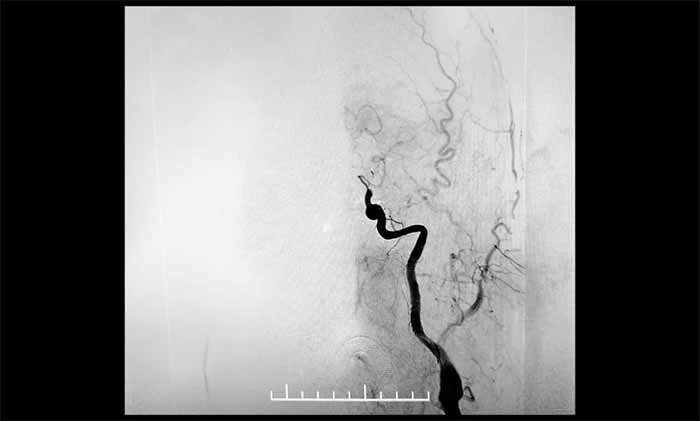

▲ DSA显示,左颈内动脉C7段闭塞

▲ 左颈内动脉顺利开通

二次取栓难度远超首次:患者处于恢复期,血管壁条件较差,存在出血转化风险。在席刚明教授指导下,王贵平博士主刀的介入团队成功取出新鲜血栓,复查造影显示血管再通,血流恢复良好。目前患者正在康复中。